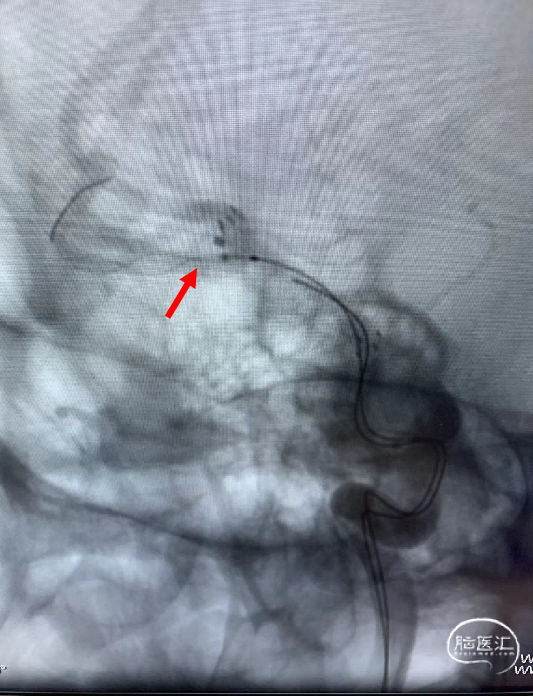

术后造影显示动脉瘤致密栓塞,不再显影;其它各分支血管通畅。

术后造影模拟血管重建显示支架头端完全覆盖动脉瘤瘤颈,并且与一期释放的支架远端形成“Kissing”。